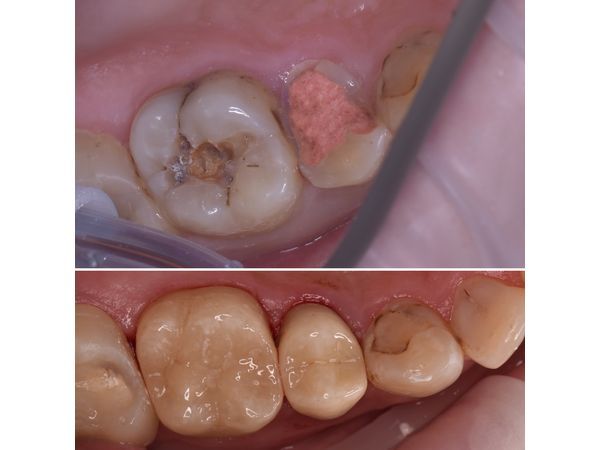

При осмотре верхних жевательных зубов справа на зубе 1.5 (премоляре) видна глубокая кариозная полость, заполненная размягчённым пигментированным дентином. Обследование дна кариозной полости стоматологическим зондом резко болезненно. Коронковая часть зуба разрушена на 70 %.

На зубе 1.6 (моляре) также имеется глубокая кариозная полость, заполненная размягчённым пигментированным дентином. Зондирование нерезко болезненно по границе эмали и дентина. Коронковая часть зуба разрушена на 50 %.

На КТ видно, что глубокая кариозная полость сообщается с камерой, где находится пульпа (сосудисто-нервный пучок). Ткани вокруг верхушек корней зубов не поражены.

На КТ видно, что кариозная полость находится в пределах дентина, т. е. пульпа не затронута. Ткани вокруг верхушек корней зубов без видимых изменений.